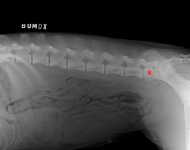

(2) 7 týdnů lat

(2) 7 týdnů lat

(2) typ 3 I

(2) typ 3 I